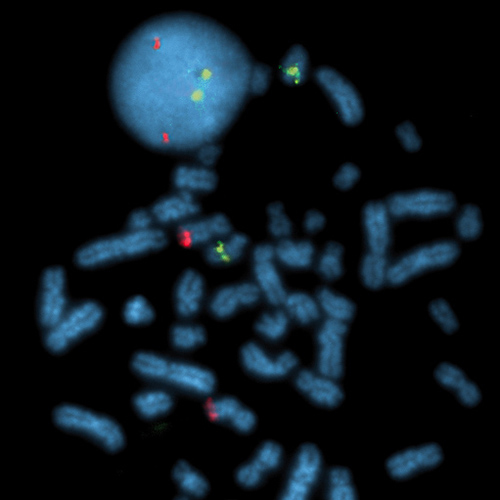

BCL2 / IGH t(14;18) probe hybridized to a normal interphase/metaphase (2R2G).

The t(14;18) chromosomal translocation is a common cytogenetic abnormality in human lymphoma and is observed in about 85% of follicular lymphoma (FL) and up to one-third of diffuse lymphomas (DL). Two breakpoint region clusters (BRC) have been identified: a major breakpoint region (mbr) within the 3' untranslated region of the BCL2 proto-oncogene (approximately 60% of the cases) and a minor cluster region (mcr) 30 kb 3' of BCL2 (approximately 25%). The BCL2 / IGH t(14;18)(q21;q32) specific FISH probe is optimized to detect the reciprocal translocation t(18;14), involving either of the two brc in the BCL2 gene in a dual-color, dual-fusion assay. Kreatech has optimized this FISH probe for the specific use on cell material (KBI-10606), or on tissue (KBI-10755).